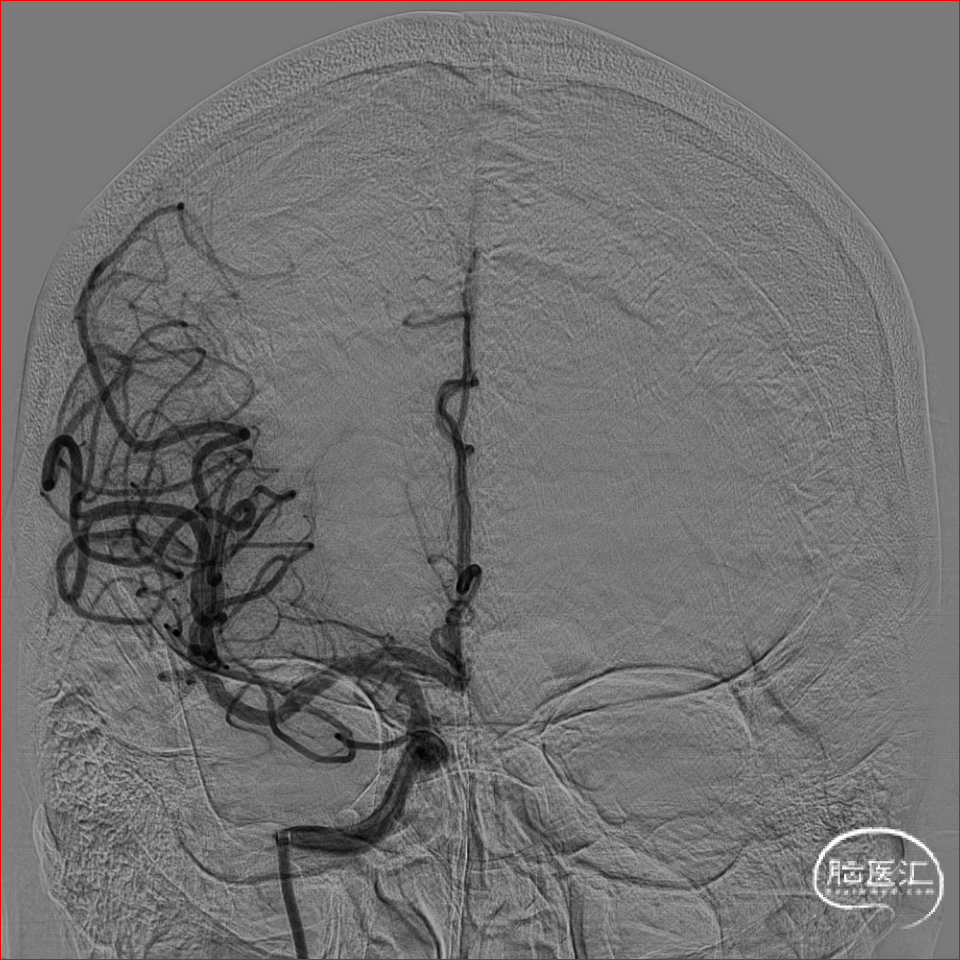

术前CTA可知责任血管为右侧大脑中动脉,遂在泥鳅导丝及4F多功能管的引导下,直接将8F导引导管送至右侧颈内动脉C1段,造影示右侧大脑中动脉M1远端下干闭塞,同侧大脑前动脉通过脑膜支向大脑中动脉供血区代偿供血,代偿ASTRIN分级2级,将SKATHI远端通路导管送至颈内动脉C4段,随后微导管(Rebar 18)在微导丝(Synchro 14)辅助下,小心通过大脑中动脉下干闭塞段至M2段,再将SKATHI远端通路导管顺利送至大脑中动脉闭塞段近端,并抵住血栓近端,撤出微导丝及微导管,用50ml注射器保持负压吸引抽吸导管,约1分钟后缓慢回撤中间导管至颈内动脉C4段,抽出多枚栓子,复查造影见右侧大脑中动脉各分支完全显影,TICI3级,血流速度正常。

术后即刻影像